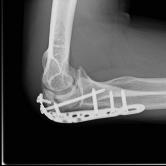

Röntgenbilder